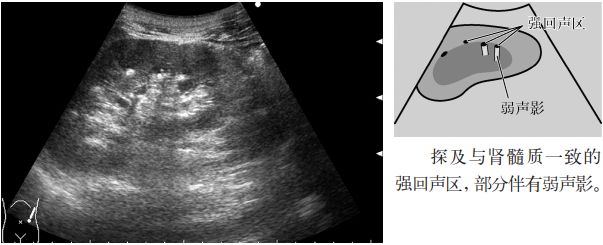

图1 肾结石

1.肾结石是指肾内伴有高回声的图像。

4.肾实质内的高回声(肾小管酸中毒或海绵肾所致的钙化)。